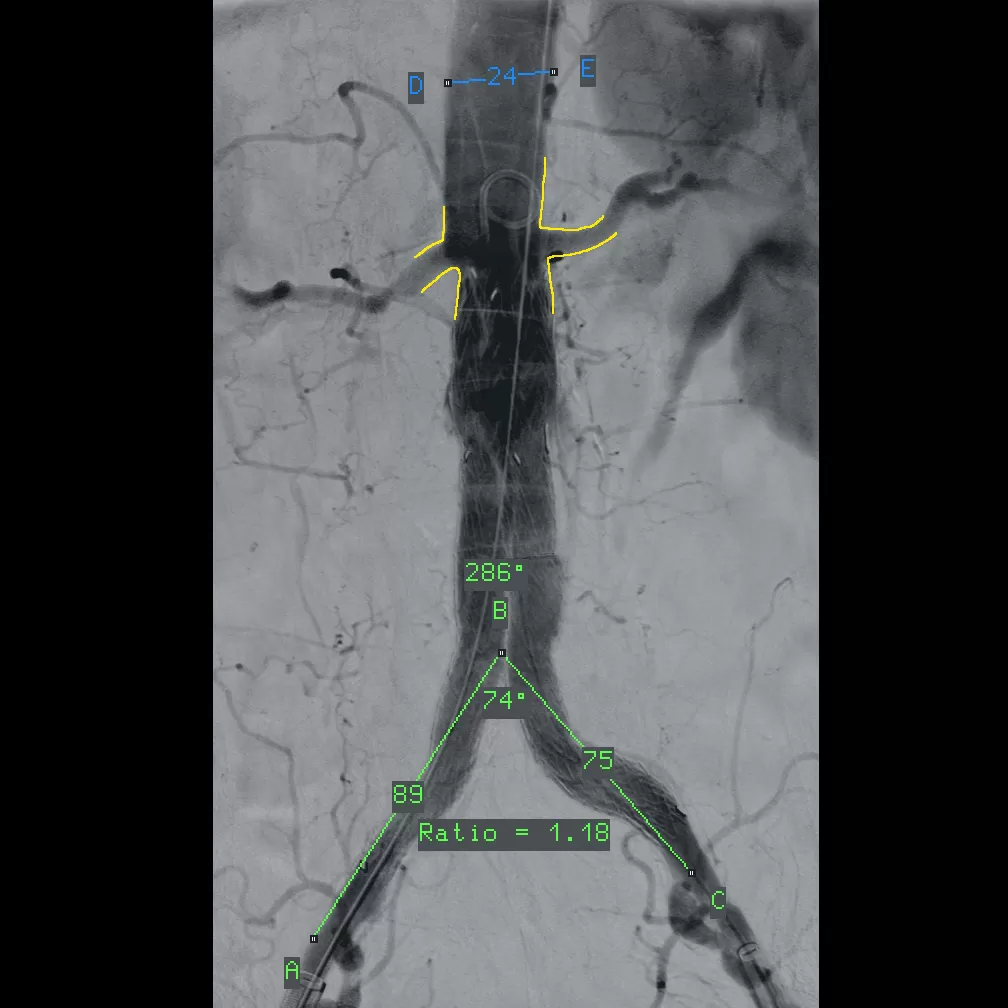

✔ Το τελευταίας τεχνολογίας ψηφιακό ακτινοσκοπικό μηχάνημα C-arm VISION RFD, χρησιμοποιείται για την διεγχειρητική ακτινοσκοπική απεικόνιση κατά την διάρκεια μεγάλου εύρους χειρουργικών επεμβάσεων.

✔ Διαθέτει την πλέον σύγχρονη τεχνολογία ψηφιακού ανιχνευτή CMOS, μεγάλου πεδίου 31x31cm με την υψηλότερη δυνατή ανάλυση 3Κx3Κ

✔ Επιπλέον εξασφαλίζει άριστη διακριτική ικανότητα ανατομικών λεπτομερειών σε συνδυασμό με την χαμηλότερη δυνατή δόση ακτινοβολίας ενώ είναι ιδανικό για υψηλών απαιτήσεων επεμβάσεις αγγειοχειρουργικής, καρδιο-αγγειοχειρουργικής, ορθοπεδικής, νευροχειρουργικής και άλλων επεμβάσεων με τα ανάλογα απεικονιστικά πρωτόκολλα.